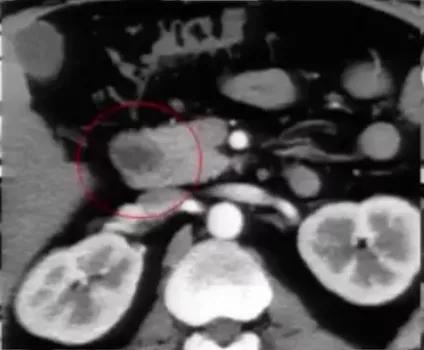

肾癌伴血管结构畸形

肾癌伴血管结构畸形患者的血管结构畸形往往容易被忽视。 在手术的过程中,如不注意就可能造成肝右叶血流的回流障碍,导致严重的临床后果。

图2:冠状位重建显示下腔静脉肝段和肝下段缺如,向上直接延续为奇静脉

图1:腹膜后方下腔静脉处于腹主动脉左侧;左肾静脉出左肾门后,汇入下腔静脉路径缩短